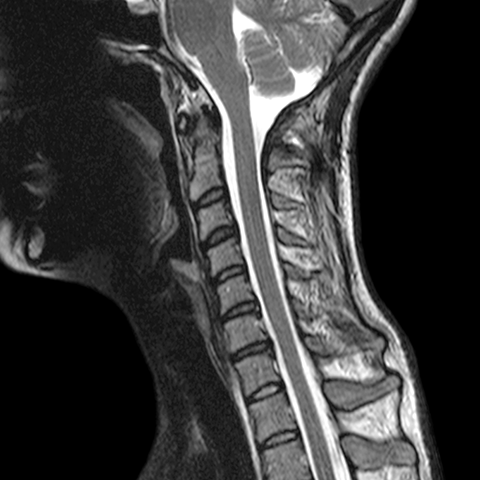

Sagittal T2 Weighted MR [6 of 8]